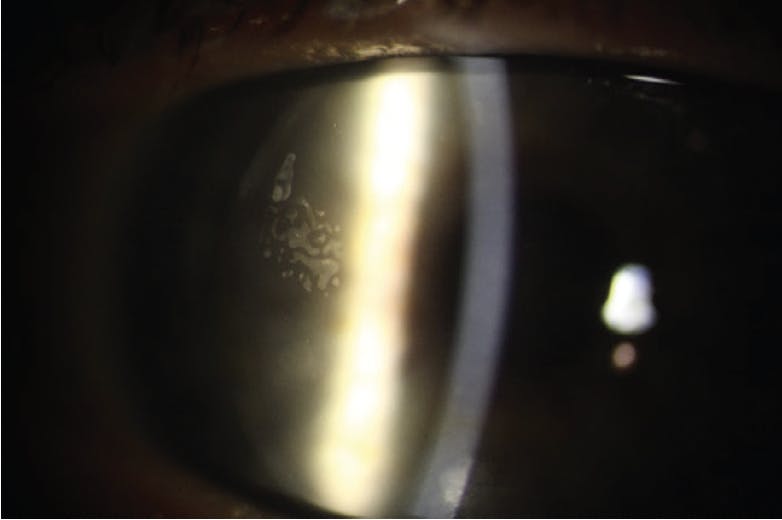

On the initial postoperative day 1 visit, it is important to ensure that the flap is in the proper position and healing correctly. Flap dislocation or full-thickness stromal folds, known as macrostriae (Figure 1), can occur due to poor flap repositioning, thin flaps, deep or highly myopic ablations, or eye rubbing.2 In any of these situations, a prompt referral back to the surgeon is necessary to refloat and smooth the flap.2 Macrostriae can be detected using direct illumination at the slit lamp and will cause a negative staining pattern when fluorescein is used.